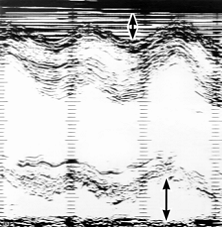

Рис. 24в). Эхокардиограмма больного с экссудативным перикардитом: изображение эхонегативного пространства за счет выпота в полость перикарда (толщина выпота отмечена двухполюсными стрелками) на одномерных эхокардиограммах, зарегистрированных на уровне нижней трети левого желудочка (эхопозитивные структуры представлены темными, а эхонегативные полости - светлыми полями)

Рис. 24б). Эхокардиограмма больного с экссудативным перикардитом: изображение эхонегативного пространства за счет выпота в полость перикарда (толщина выпота отмечена двухполюсными стрелками) на одномерных эхокардиограммах, зарегистрированных на уровне средней трети левого желудочка (эхопозитивные структуры представлены темными, а эхонегативные полости - светлыми полями).